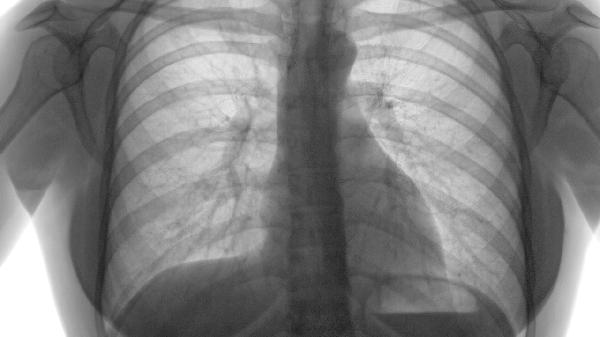

第一秒用力呼气容积每年下降≥50ml提示预后不良,需加强治疗。6分钟步行距离每3个月评估,改善<30米需调整方案。急性加重频率每年>2次者需升级治疗层级,血清C反应蛋白持续升高者疗程延长20%-30%。